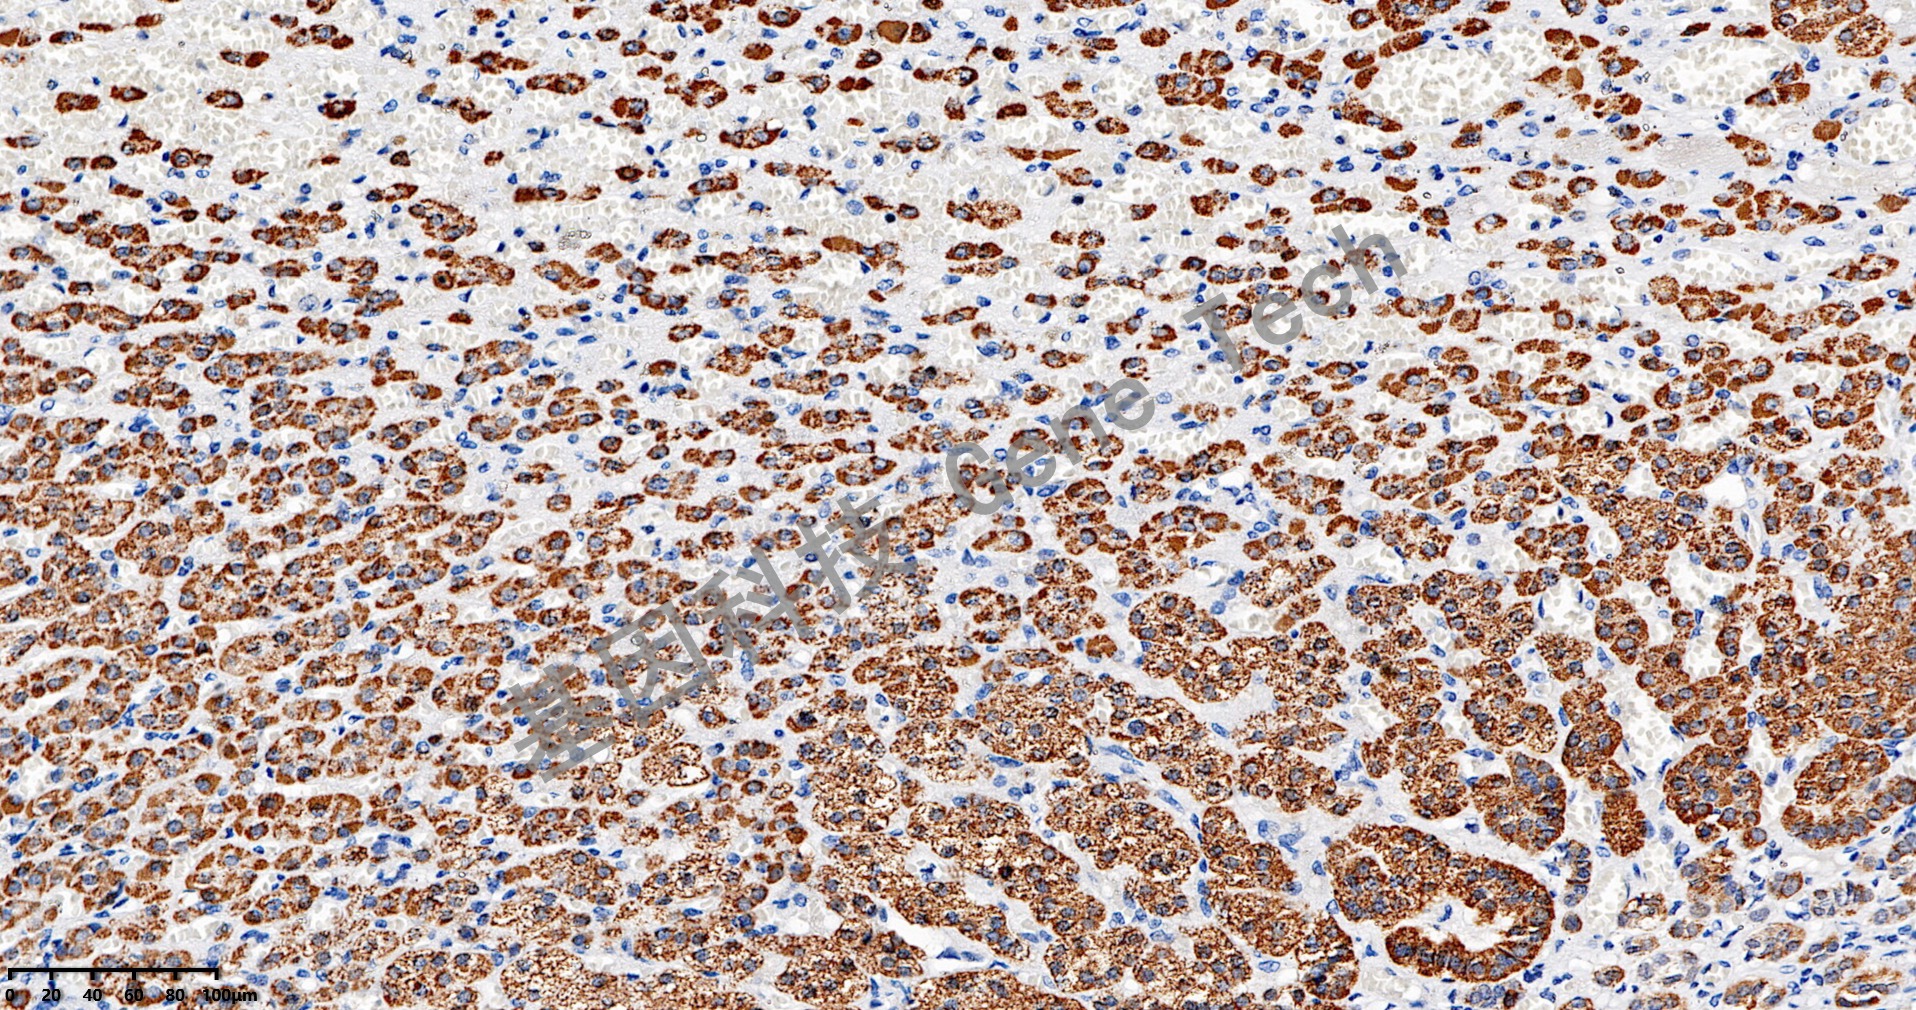

| 肾上腺皮质石蜡切片,用 CYP11B1(GT2583)染色,细胞浆阳性,DAB 显色。 | ||